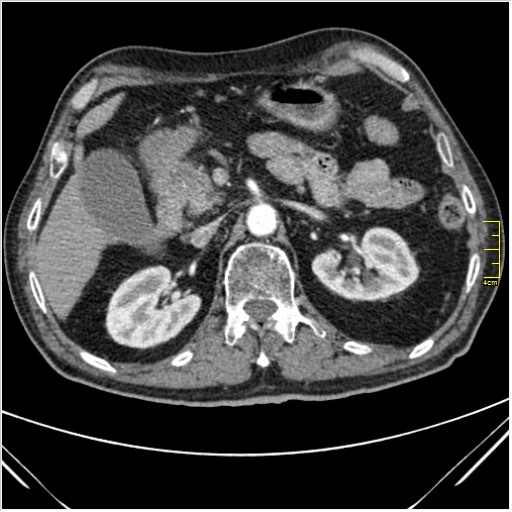

Мужчина 62 года с желтухой

Опухоль головки поджелудочной железы, расширение холедоха и панкреат. протока (Double Channel sign)

Карциномы панкреас гиподенсны на КТ с болюсом, т.к. содержать много соединительной и фиброзной ткани, в отличие от нормальной ткани железы, которая (как любая железа) хорошо васкуляризирована. Поэтому если видим в панкреас солидное гиподенсное образование - всегда настораживает на предмет рака. Второй момент: обязательная оценка взаимоотношения опухоли к ВБА и ВБВ, на предмет оценки операбельности.